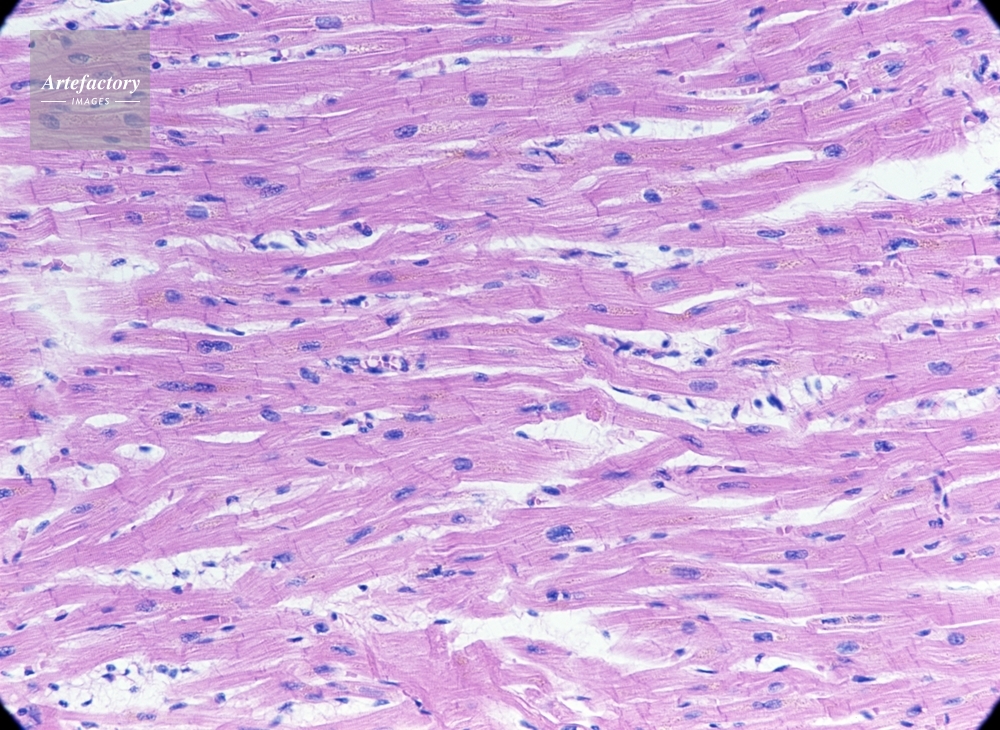

| 作品タイトル | ヒト・心筋 | モデルリリース | なし | |

| キャプション | ヘマトキシリンエオシン染色長辺55mmで100倍 | 制限事項 | ||